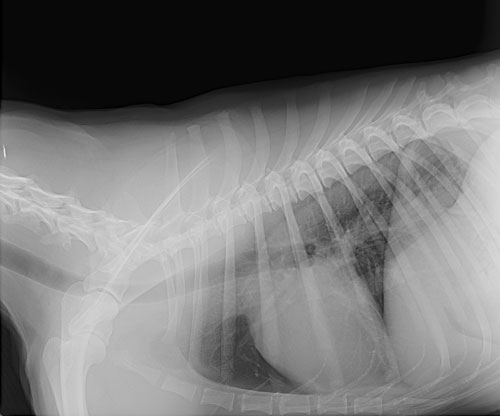

We use state-of-the-art digital radiography to take 'x-rays' of patients of most sizes. Digital radiography captures x-ray images on an electronic screen, converts them to a digital format, and displays them on a computer monitor, eliminating the need for film, chemicals, or an x-ray darkroom. Computer software allows us to enhance or enlarge the images which make it easier to evaluate patients. We can also send your pet's radiographs to a specialist for a consultation so you can even look at them at home.